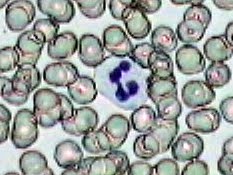

Práctica de Frotis sanguíneo 24